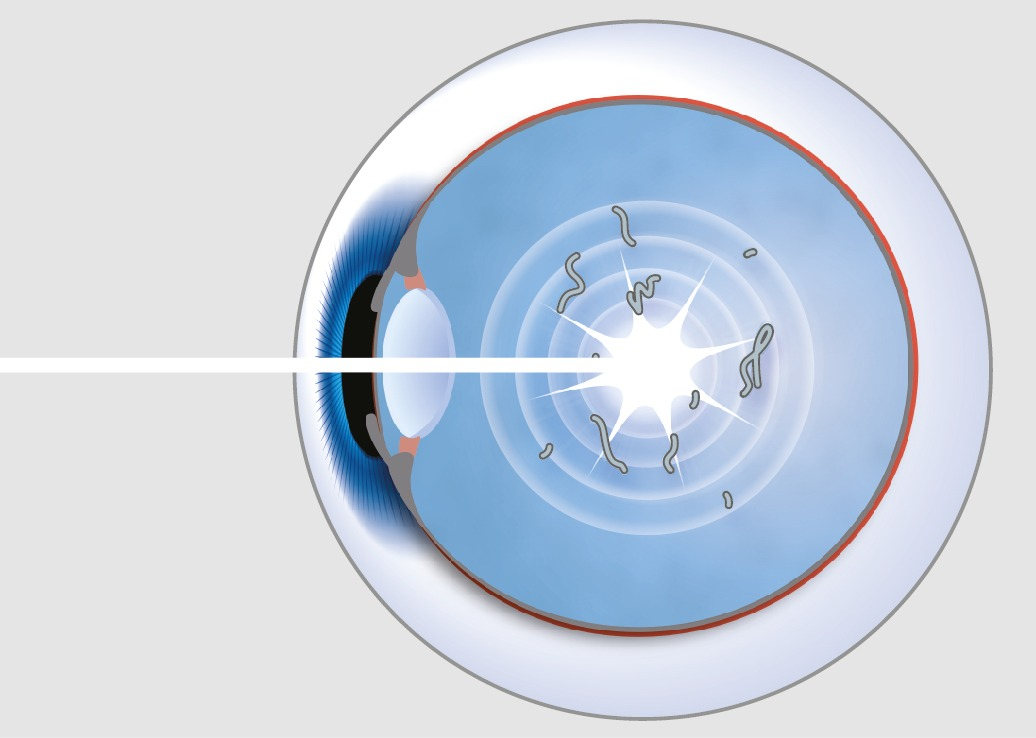

Eye Floaters are spots in your vision caused by aging of the vitreous gel inside the eye. Although they are often benign, they can cause disturbance to the vision by casting shadows on the retina and appearing as black specks, strings or cobwebs. They may sometimes be associated with retinal tears which require Argon Laser treatment to seal the tears and prevent retinal detachment. NOVENA Bladeless Cataract Surgery & Eye Specialist Centre offers another type Nd: YAG cold laser to treat problematic floaters. This form of laser therapy is also called Laser Floater Vitreolysis.

LFR is a non-invasive procedure that can treat visual disturbance caused by eye floaters. LFR applies nanosecond pulses of laser light to evaporate vitreous opacities (floaters), converting them into gas, resulting in their removal / reduction in size.